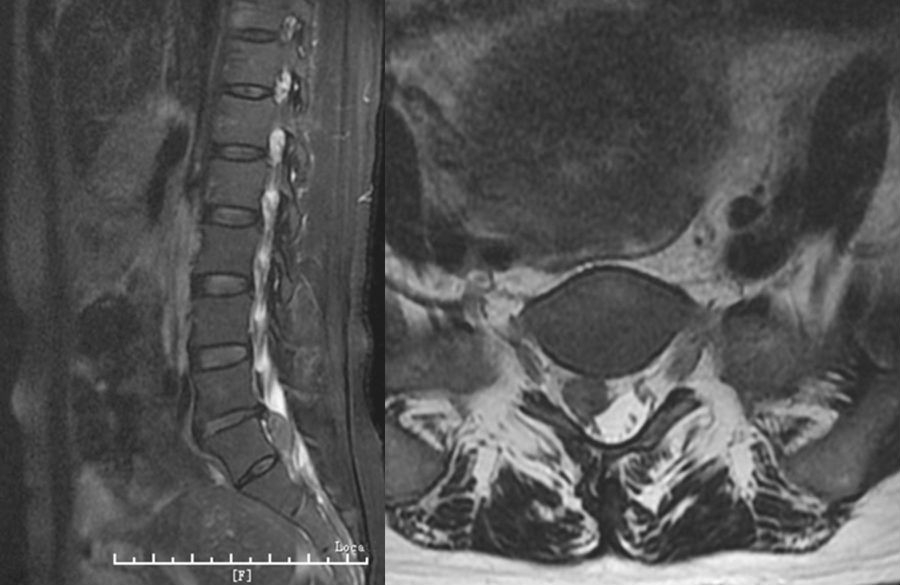

纤维环完全破裂,髓核突向椎管,仅有后纵韧带或一层纤维膜覆盖,表面高低不平。此类型常需手术治疗。(图1)

3. 脱垂游离型

破裂突出的椎间盘组织或碎块脱入椎管内或完全游离。此型容易导致马尾神经症状,常需手术治疗。(图2)

图1 腰椎磁共振显示中央突出型的L4-5椎间盘

图2 腰部磁共振显示脱垂游离型的L5-S1椎间盘